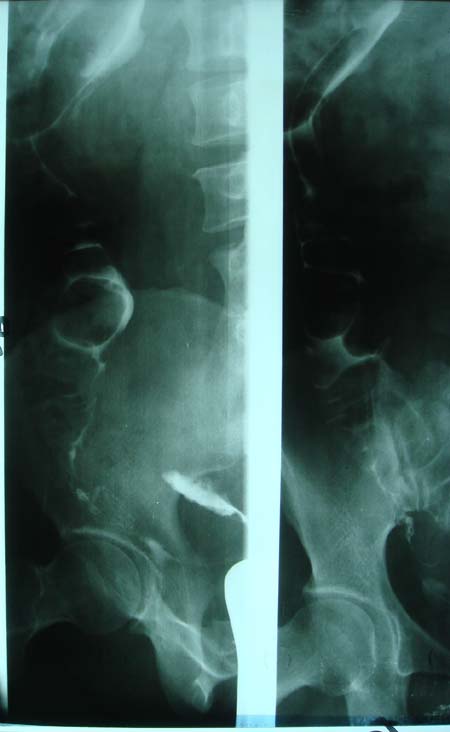

以下是引用dyqct在2009-8-23 16:17:00的发言:[br]考虑:1、造影剂进入腹腔、结肠旁沟、肝周;[br] 2、子宫明显增大(腺肌增生症?);[br] 3、膀胱显影是由于造影剂吸收后经肾分泌进入膀胱的;[br] 4、建议mri检查子宫。